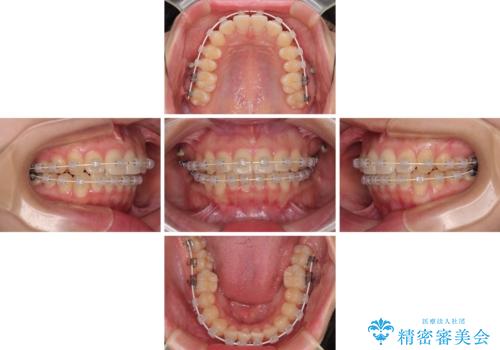

- 矯正装置

- 審美装置

- 治療期間

- 1年1ヶ月

- 上下前歯のデコボコを気にして来院された患者様です。

ワイヤー矯正でもマウスピース矯正でも可能でしたが、短期間で、自身の手を煩わせることなく治療を行いたいとのことで、ワイヤー装置にて矯正治療を行うこととしました。

舌の突出癖により、出っ歯仕上がりとなる可能性がありましたが、舌のトレーニングを頑張っていただき、1年強で終えることができました。